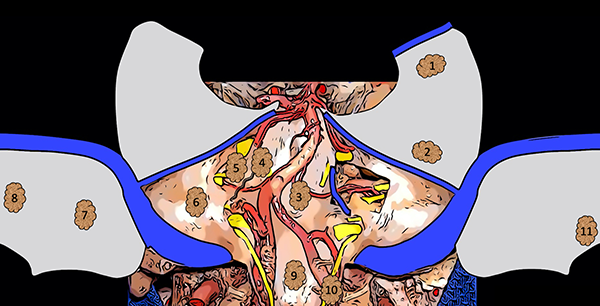

La figura 12 es un dibujo esquemático que sintetiza la presente clasificación (Figura 12).

Figura 12. Dibujo esquemático de la clasificación de los meningiomas de fosa posterior. 1: Meningioma tentorial medial; 2: Meningioma tentorial lateral; 3: Meningioma clival; 4: Meningioma petro-clival; 5: Meningioma petroso anterior; 6: Meningioma petroso posterior; 7: Meningioma de la convexidad lateral; 8: Meningioma de la convexidad medial; 9: Meningioma del foramen magno anterior; 10: Meningioma del foramen magno lateral; 11: Meningioma del foramen magno posterior.